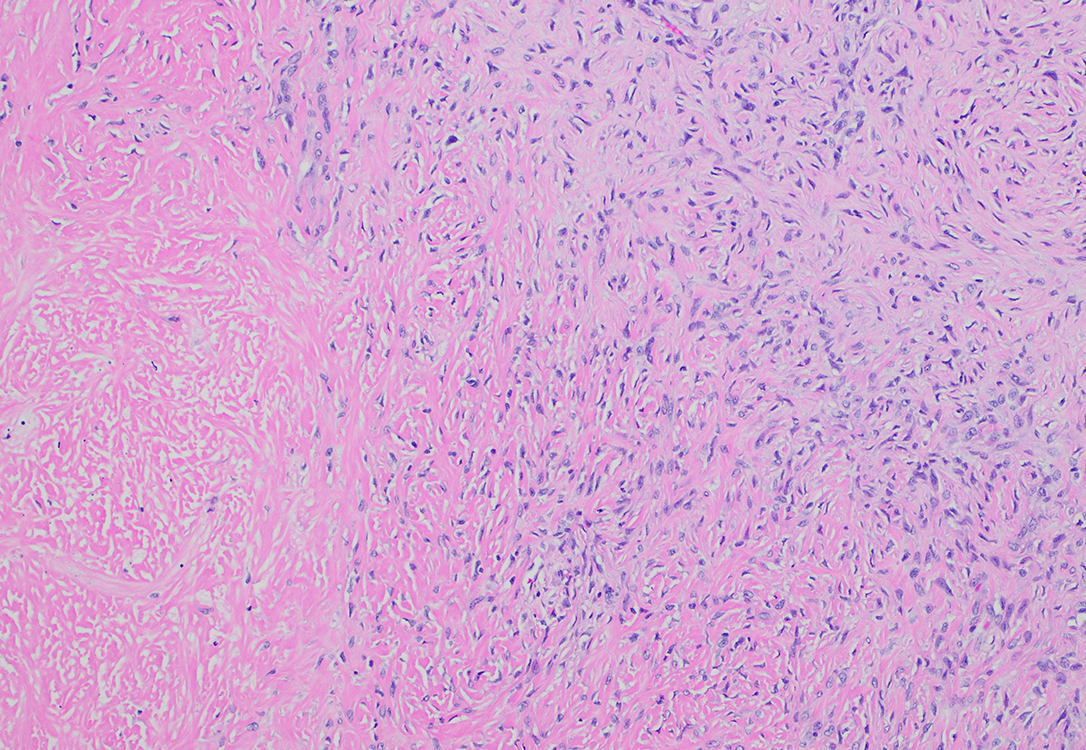

FIgure 2 Low power